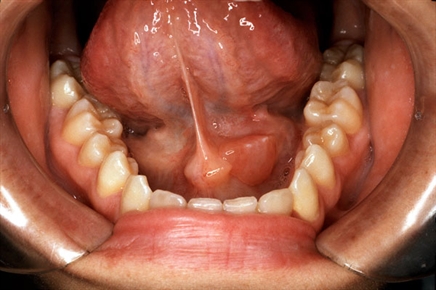

أعراض التهاب الغدد اللعابية يوجد العديد من الأعراض المصاحبة لالتهاب الغدد اللعابية، يذكر منها ما يأتي: عدم القدرة على فتح الفم بالكامل. الانزعاج أو الألم أثناء تناول الطعام وعند فتح الفم.الشعور بوج ... اقرأ المزيد